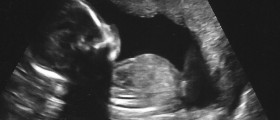

So i had a miscarrage at the beginning of auguest and had my first period on time and then it wasnt on time in september and then october lasted 3 days and started the 5th.Then this past week it started sunday night and was pretty red to start out but the next morning went brown and not much only when i wipe and the next day was nothing.Im just wondering what people think it might be.we do have un protected sex and we do want a baby but for some reason we havent gotten pregnant yet...thanks